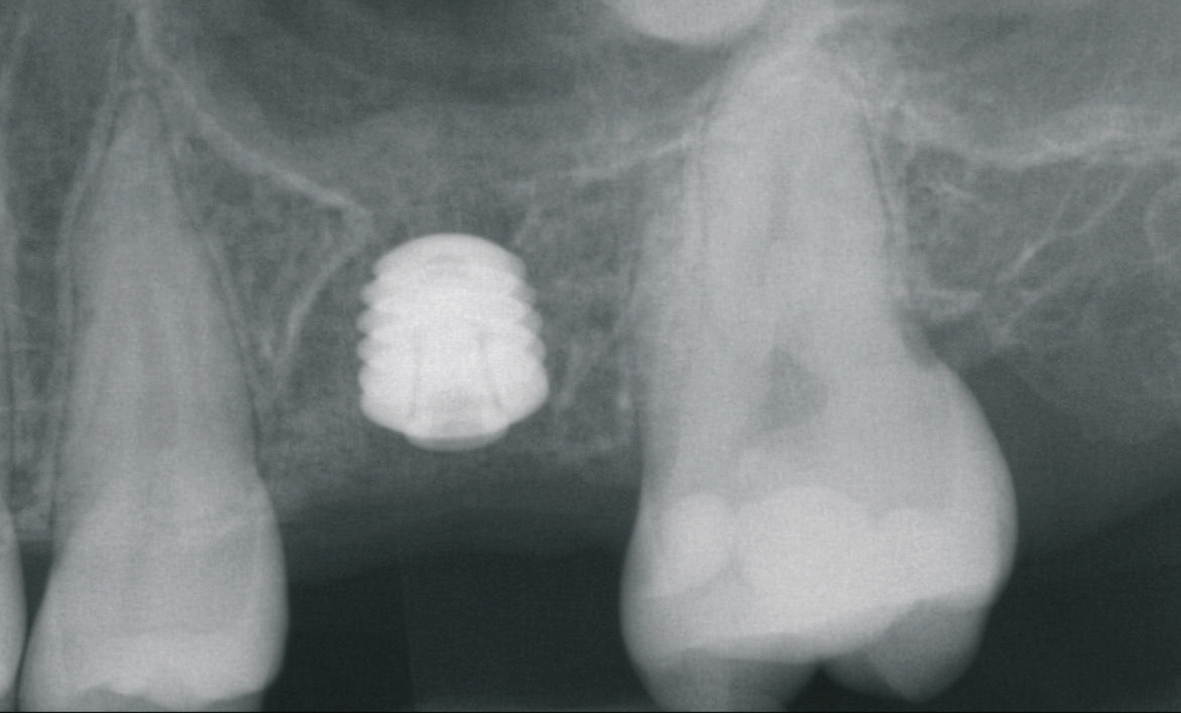

Beim Fehlen von mehreren Zähnen können unterschiedliche Planungs- und Versorgungskonzepte zur Anwendung kommen. Zur Kompensation der geringeren Verankerungsfläche von kurzen Implantaten im Knochen wird neben der Zahn-für-Zahn-Versorgung eine Verblockung von multiplen Implantaten empfohlen [6]. Die Empfehlungen sind aber im Kontext der jeweiligen Implantat- Aufbau-Verbindung, die bei der Versorgung von kurzen Implantaten zur Anwendung gekommen ist, zu berücksichtigen. Aus dem Anwendungsbereich der Implantate mit einer externen Implantataufbauverbindung wird eine Verblockung angeraten, um eine ausreichende Stabilität besonders bei einer hohen Aufbauhöhe des Zahnersatzes sicher zu stellen [6]. Die Erfahrung bei der Anwendung von Implantaten mit einer konischen Implantataufbauverbindung hat gezeigt, dass sich multiple Einzelkronen langzeitstabil eingliedern lassen [2] (Abb. 9-14). Besonders in Hinblick auf das periimplantäre Knochenniveau wird davon ausgegangen, dass sich bei der Einzelversorgung keine Spannungen auf Grund einer unzureichenden zahntechnischen Herstellungsgenauigkeit ergeben können.